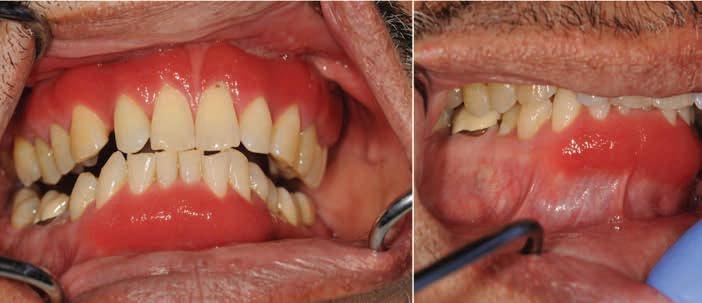

A 62-year-old male patient presented with a chief complaint of red, sore, and bleeding gums while brushing. The patient reported that he started noticing these symptoms approximately 2 years ago which has progressively worsened over time. The patient’s general dentist recommended deep cleaning, however that did not help resolve his problems. Subsequently, patient was referred to a periodontist for further evaluation and treatment. His initial periodontal therapy consisted of plaque control, scaling and root planing which resulted in limited improvement of his gingival condition. Patient could not recall taking any new medications or any other possible triggers for this condition. The patient’s medical history was unremarkable,

Figure 1. Maxillary and mandibular facial gingivae appear swollen and fiery red with sharp demarcation at the mucogingival margin.

and he denied any current or past use of tobacco products. Patient reported he did not have any rashes or itchy areas on his skin or genital mucosa. Clinical examination revealed generalized, enlarged, edematous and erythematous maxillary and mandibular facial gingiva, predominantly the anterior region. The affected gingiva revealed sharp demarcation along the mucogingival margin and between involved and uninvolved gingiva (Figure 1). The affected gingiva appeared swollen, fiery red in color, with a shiny granular surface

expression

texture with loss of stippling (Figure 1). Affected gingiva was mildly tender to palpation, revealed no evidence of ulcerations or erosions and periodontal probing elicited profuse bleeding. Rest of the oral soft tissue examination was unremarkable. Given the clinical presentation, his periodontist suspected desquamative gingivitis secondary to autoimmune vesiculo-erosive diseases and took incisional biopsies from the affected gingiva and submitted routine histopathologic and direct immunofluorescence studies.